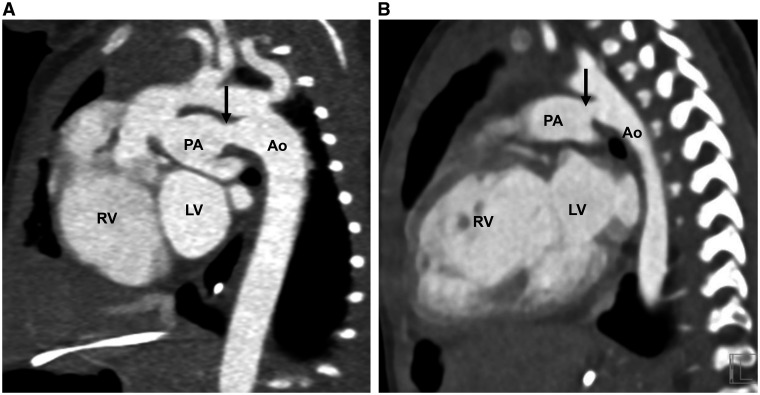

Photon-counting detector computed tomography (PCD-CT) is the most recent advancement in CT technology and has the potential to change clinical practice. Unlike conventional energy-integrated-detector (EID) that uses a two-step process to convert X-rays into a digital signal, PCD-CT directly converts photon energies into electronic signal. The advantages of PCD-CT over EID-CT are higher spatial resolution, electronic noise reduction, higher contrast-to-noise ratio, improved radiation dose efficiency, and intrinsic spectral imaging. Successful implementation into clinical practice requires adaptations in CT protocols. In this review, we summarize the basic principles of PCD-CT and technical scanning factors followed by a discussion of its clinical benefits in pediatric pulmonary and cardiovascular imaging.